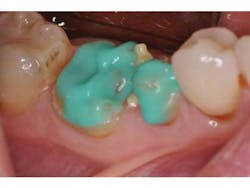

A patient presents with splinted provisional crowns on teeth Nos. 29 and 30 (Fig. 1). The provisionals were splinted to aid retention during the laboratory fabrication phase. The treatment plan called for all-ceramic restorations that could take advantage of resin cement bonding technology, thus the preparation margins were kept supragingival. Lithium disilicate restorations (e.max, Ivoclar) were created monolithically, meaning that no veneering feldspathic porcelain was required (Fig. 2).

After removal of the provisional restorations, the restorations are tried in and assessed for fit. Although this step is necessary, it will contaminate the intaglio surface of the restorations with moisture and bacteria and thus decrease final bond strength.(5) Before application of silane, the intaglio surface should be cleaned with solution to remove any surface contamination before application of silane (Fig. 3). Studies have shown that a proprietary solution (Ivoclean, Ivoclar) is more effective than water or phosphoric acid gel at restoring precontamination conditions of zirconium oxide. (6) An unpublished internal study revealed similar results for lithium disilicate. (7)